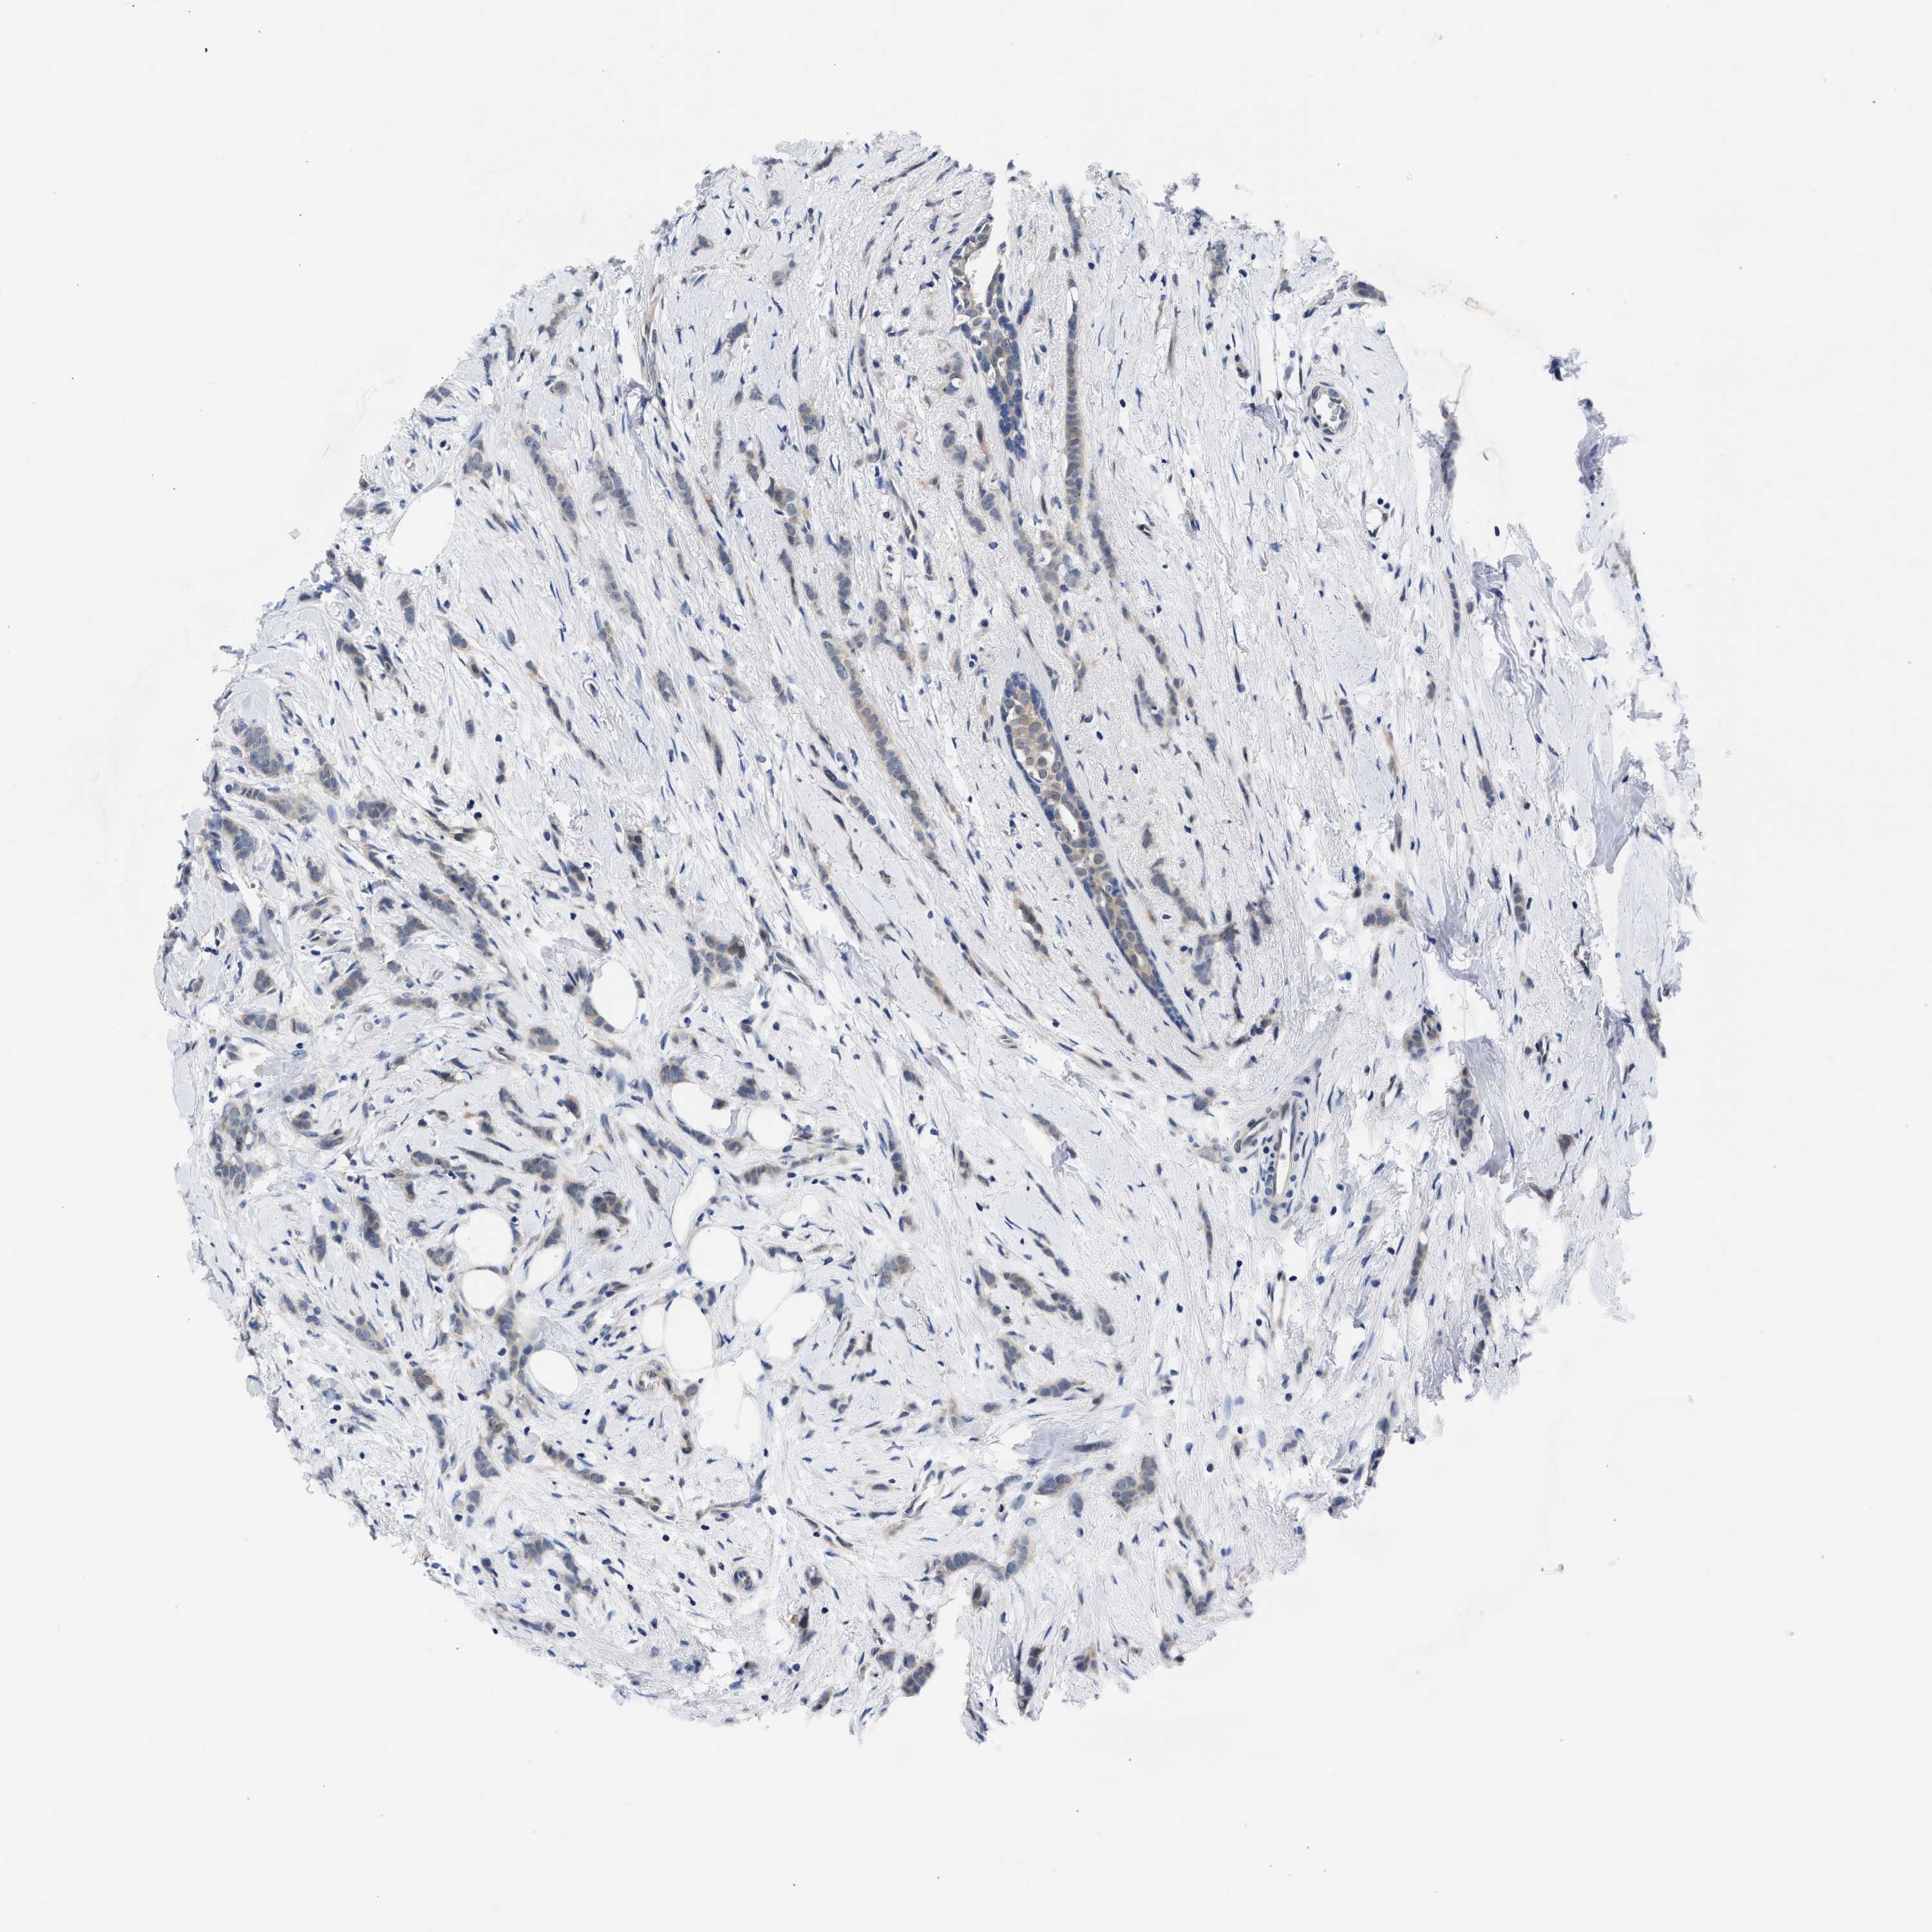

BRCA TCGA BRCA VALIDATION PROTEIN EXPRESSION